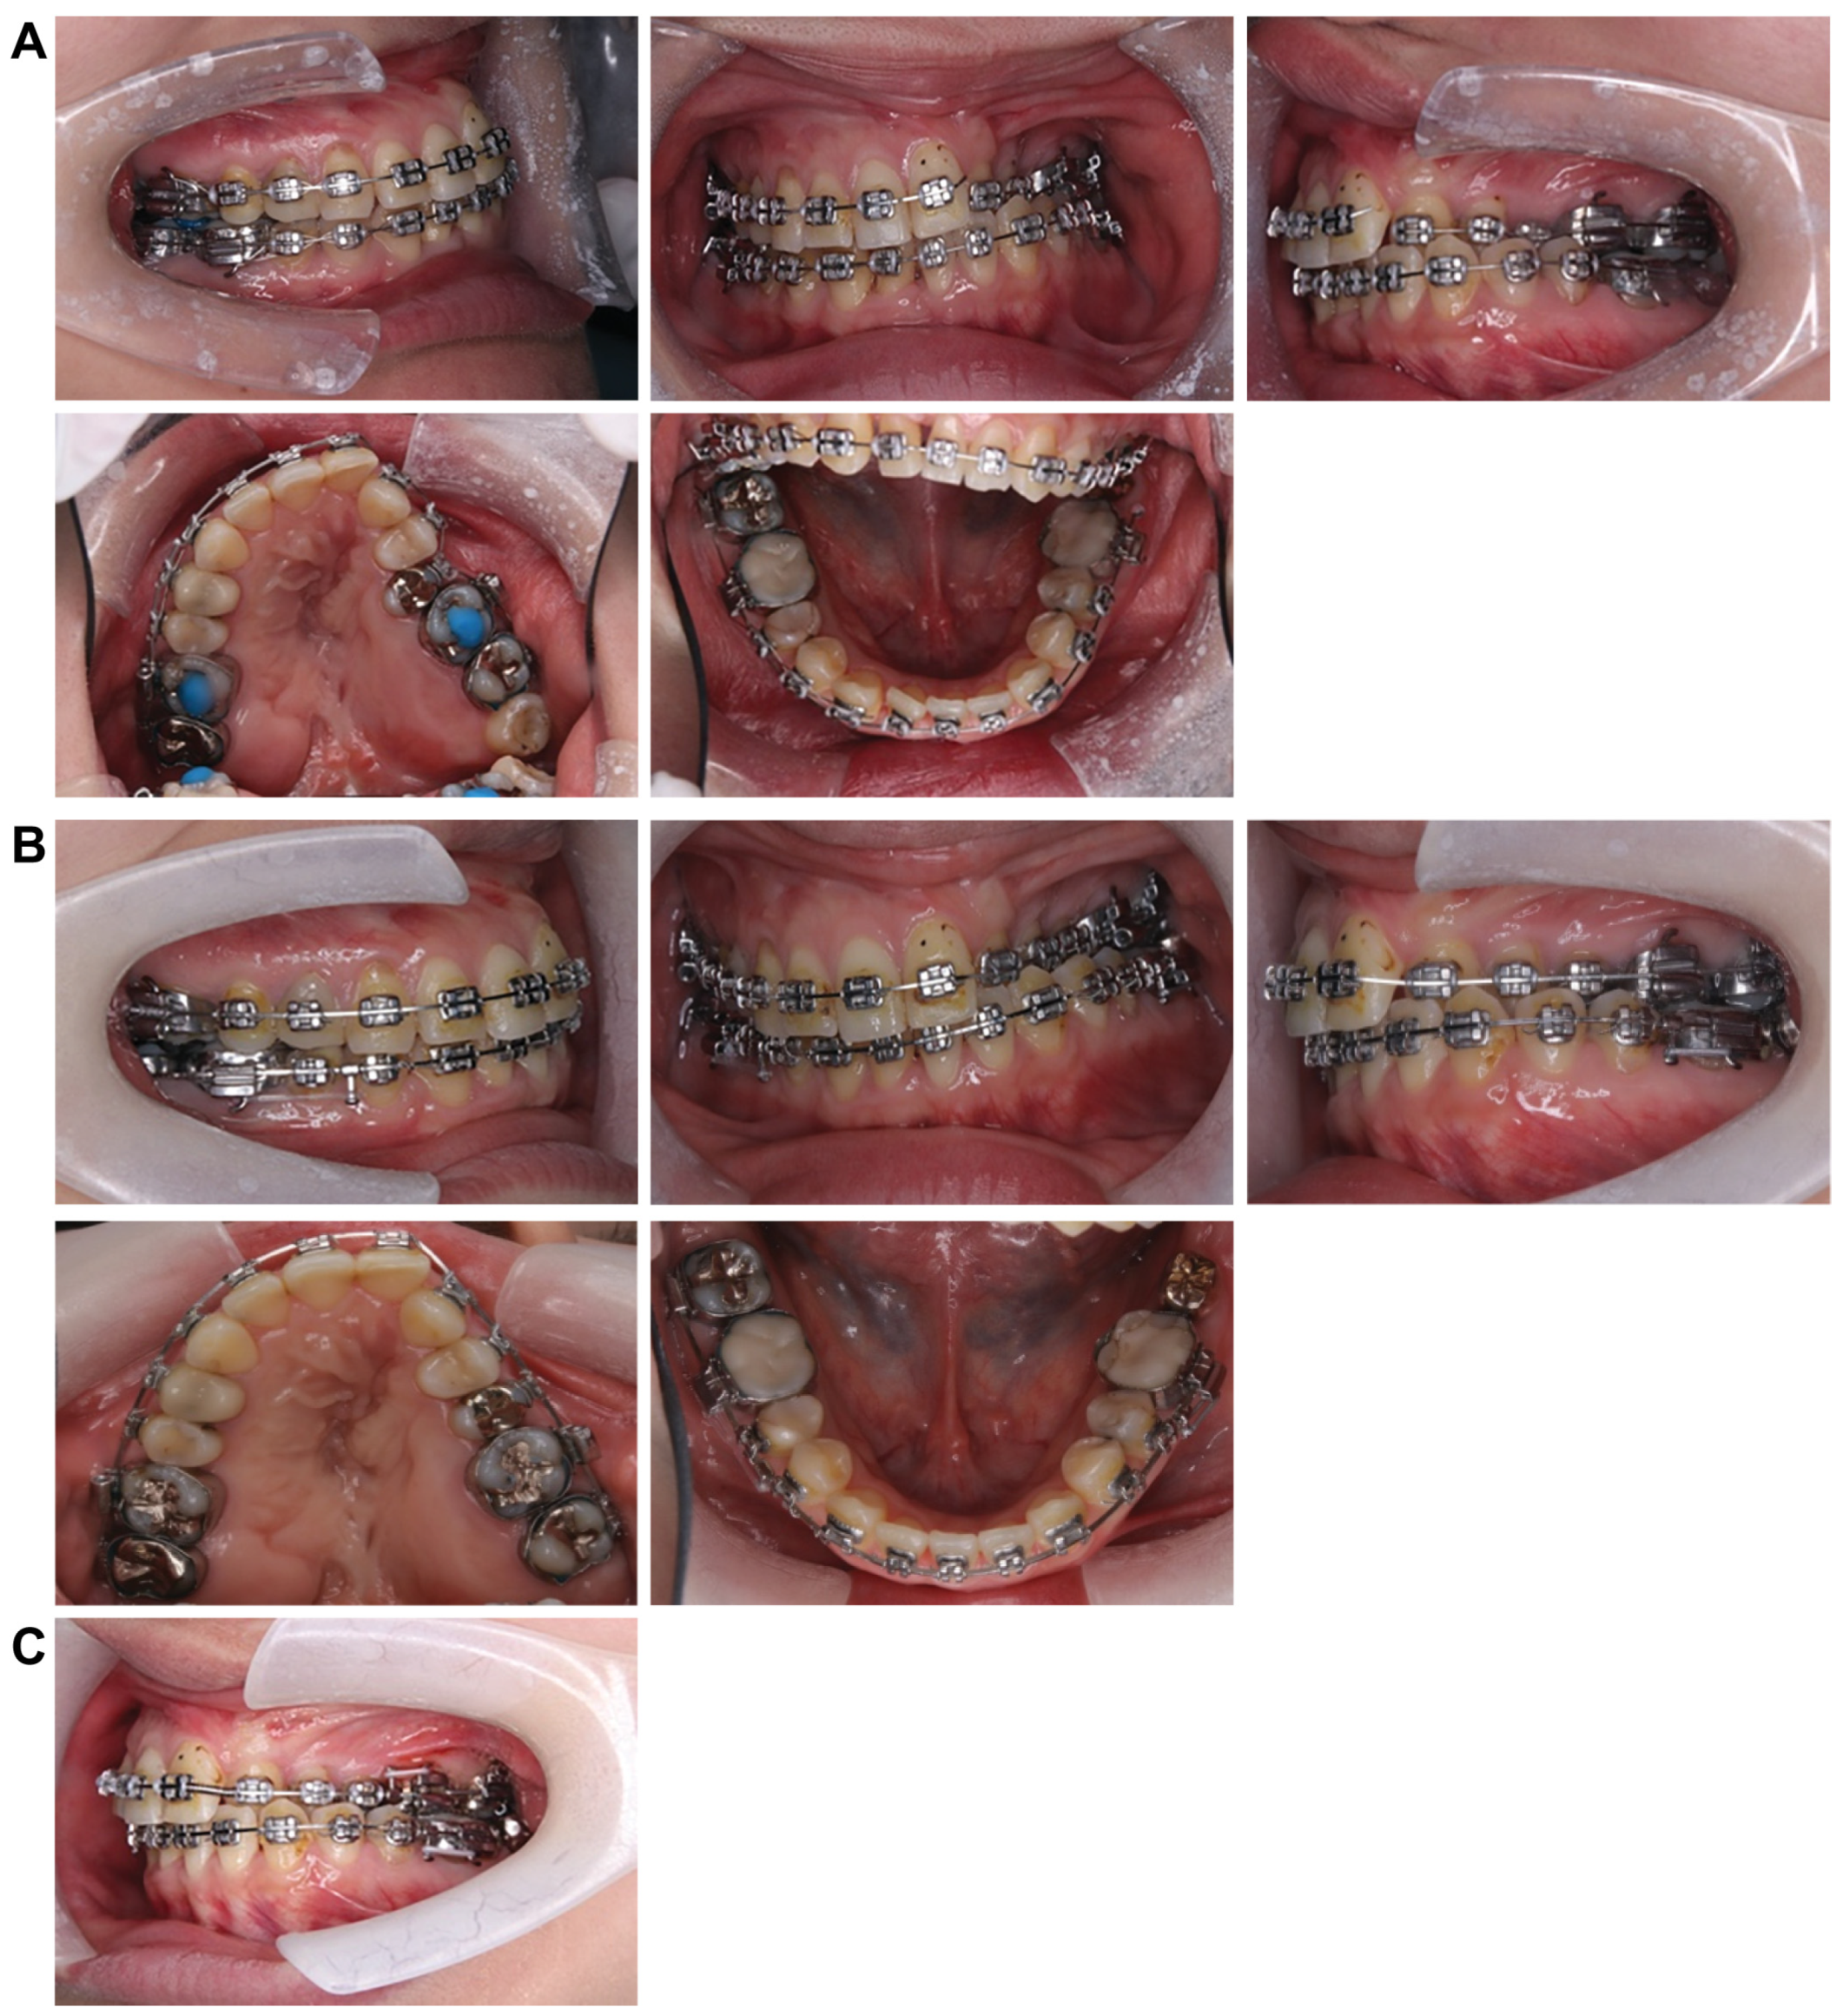

Treatment progress: During preoperative orthodontic treatment, owing to the significant asymmetry in the left and right maxillary dental arches, leveling was initiated using a sectional arch, dividing the maxilla into two segments: from the right second molar to the left central incisor and from the left canine to the left second molar. The mandibular right lateral incisor, which exhibited lingual displacement, was extracted, and a multi-bracket device (0.022 slot pre-adjusted appliance) was placed. After leveling was completed in the maxilla, the treatment transitioned to a continuous arch to minimize intraoperative movement while improving the arch width. Subsequently, to facilitate the multi-segment Le Fort I osteotomy, an open coil spring was placed between the left central incisor and the canine to gain the necessary osteotomy width. In the mandible, the extraction space from the right lateral incisor was used to improve crowding and space closure was performed (Figure 5). Dental photographs taken just before surgery confirmed that a 3.0 mm space was achieved for the surgical procedures necessary for the multi-segment approach, at which point the arch was switched to a sectional arch (Figure 6). After 15 months of treatment, preoperative orthodontics were nearly completed, and preoperative records were obtained. Crowding in the mandible was resolved, and the arch of the maxilla approached an ovoid shape with approximately 4.0 mm of expansion in width; however, the occlusion on the right side remained a crossbite (Figure 7). During orthognathic surgery, a rolling movement of 6.0° to the right was performed around the left first molar to correct the left-sided cant of the occlusal plane. A 5.0° posterior impaction centered on the anterior nasal spine and a 2.0 mm parallel shift to the left were also performed to improve the deformity and align the midline. Furthermore, a multi-segment Le Fort I osteotomy was performed to expand the maxilla by 5.0 mm from the left canine to the second molar, correcting the maxillary and mandibular arch asymmetry. During this process, a releasing incision was made at the palatal scar site, using a chisel and mallet for osteotomy.

Figure 5.

Treatment progress. (A) Attach nickel titanium wires to the upper and lower jaws and begin leveling. (B) After extracting the mandibular right lateral incisor, attach an angle wire and continue to level. (C) Contain the upper maxilla wire and improve the width and diameter.

Figure 6.

An open coil creates a space between the upper right central incisor and canine to create a gap for the bone chisel.

Figure 7.

Preoperative intraoral photograph and radiographs and CT. (A) Intraoral photographs. (B) Panoramic radiograph. (C) Cephalograms and CT.